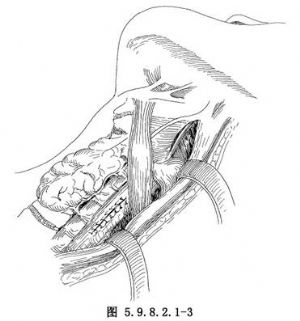

食管穿孔較爲少見,但隨着診斷技術和對本病認識的不斷提高,又由於大量開展食管內鏡檢查和食管擴張治療等,食管穿孔的發生率較過去明顯增加。引起食管穿孔的主要原因有:①損傷性食管穿孔,損傷性食管穿孔可可由槍彈傷、刀刺傷引起。胸骨與脊柱間突然受壓的閉合性胸部外傷也可能導致食管破裂,但由於食管位於後縱隔內,與心臟大血管等重要臟器相鄰,因此單獨引起胸內食管損傷者罕見,常合併心臟大血管損傷,多來不及搶救而死亡。臨牀見到的多爲頸部食管穿孔。除上述原因外,國內曾有多起輪胎爆炸,氣浪衝擊經口腔使食管發生破裂的報道。②醫源性食管穿孔,主要在食管內鏡檢查(圖5.9.8.2.1-0-1)、食管狹窄擴張、食管腔內置管、食管異物取出等診治過程中發生,多因操作不慎或食管有潛在病變而導致穿孔。其發生率佔食管穿孔的60%~70%。③異物性食管穿孔,異物性食管穿孔發生率僅次於醫源性食管穿孔。常見的原因是誤吞魚骨、雞骨、義齒等,大多爲不規整、銳利或體積較大的異物,可直接刺穿食管壁或壓迫使食管壁壞死或巨大異物使食管壁撕裂穿孔。④腐蝕性食管穿孔,吞服大量強酸或強鹼性腐蝕劑,可造成食管全層的嚴重損傷及食管穿孔。⑤自發性食管穿孔,自發性食管穿孔的原因目前尚不清楚,多與大量飲酒及暴食後發生嘔吐有關,嘔吐使腹內壓突然增高,擠壓胃部使食管腔內壓力驟然增高,同時環嚥肌反應性痙攣呈收縮狀態,致使管腔內壓力和胸腔內壓力在瞬間相差很大,引起食管破裂。偶爾也可發生於腹部用力動作時,如作嘔、分娩、癲癇抽搐、哮喘、舉重或大便等。食管穿孔後,有強烈刺激作用的胃內容物及帶有各種細菌的口腔分泌物和食物迅速經破口進入縱隔,引起嚴重的縱隔感染。由於縱隔爲疏鬆結締組織,再加上負壓及心臟大血管搏動等因素,易導致炎症在縱隔內迅速擴散,並可侵蝕穿破胸膜進入胸腔,形成一側或雙側液氣胸。縱隔及胸腔嚴重感染,胸膜腔大量滲出及毒素吸收,可很快發生休克(圖5.9.8.2.1-0-2)。吞嚥使空氣由破口進入胸膜腔,造成張力性氣胸,更加重呼吸、循環功能紊亂(圖5.9.8.2.1-0-3)。若爲腐蝕性或異物導致的食管穿孔,可引起鄰近大血管的損傷及發生大出血,如不及時救治,患者可迅速死亡。

食管穿孔治療的成敗取決於穿孔部位、裂口大小、確診時間及治療措施是否得當。穿孔時間超過24h者,其傷死率比早期治療的高3倍多。食管穿孔治療方案的制定、手術方法的選擇應根據具體情況做出。總的原則是:①消除污染來源;②充分引流;③抗生素應用;④維持水電解質平衡及足夠的營養。